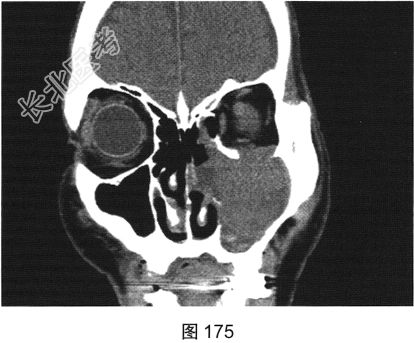

- [材料题] 患者男性,75岁。左侧颌面部肿胀6个月,局部压痛,伴有左侧鼻塞、流涕。CT检查结果如图173~图176所示。

- 简答题1、请问该患者CT表现是什么?

- 简答题2、请问最符合该患者的初步诊断是什么?

- 简答题3、请问属于上颌窦恶性肿瘤有哪些?

- 简答题4、请问翼腭窝受侵主要见于哪种疾病?